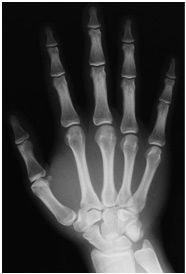

| PA Hand | ANATOMY: entire hand including 1'' of distal radius and ulna CRITERIA: equal concavity on either side of digits digits separated with no superimposition open joint spaces POSITIONING: CR perpendicular @ 3rd MCP joint |

| Oblique Hand | ANATOMY: entire hand including 1'' of distal radius and ulna CRITERIA: digits more concave to one side minimal overlap of 3rd-5th metacarpal shafts separation of the 2nd and 3rd metacarpals POSITIONING: CR perpendicular @ 3rd MCP joint |

| Lateral Hand | ANATOMY: entire hand including distal 1'' of radius and ulna superimposed CRITERIA: metacarpals and distal radius/ulna are superimposed thumb is free of superimposition *thumb in lateral position* open joint spaces POSITIONING: CR perpendicular @ 3rd MCP joint LAT Extension: foreign body localization LAT Flexion: phalanges |